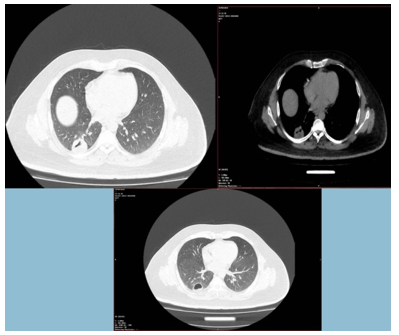

Upon admission, the patient presented with stable hemodynamics, maintaining an oxygen saturation of 98% without supplemental oxygen. High-resolution computed tomography (HRCT) of the chest identified a pulmonary cavity, prompting differential diagnoses of TB or a fungal infection. Initial laboratory analyses revealed normal leukocyte counts; however, inflammatory markers were elevated (Table 1). Abdominal ultrasonography indicated grade 2-3 hepatic steatosis, with no evidence of hydatid cysts. This finding was supported by a negative serum anti-hydatid IgG enzyme-linked immunosorbent assay (ELISA). Subsequently, a flexible bronchoscopy was performed, and BAL fluid was collected from the right lower lobe. The samples were submitted for a comprehensive array of analyses, including bacterial and fungal cultures, three acid-fast bacilli (AFB) smears, mycobacterium TB polymerase chain reaction (MTB-PCR), Lophomonas microscopy, and cytological examination. Bacterial and fungal cultures, AFB smears, and MTB-PCR yielded negative results. However, microscopic examination of BAL fluid revealed the presence of Lophomonas spp. (Figure 1). Further supporting a parasitic etiology, serum IgE levels were elevated at 387 IU/mL (Normal range: <160 kU/L). A spiral CT scan of the lungs identified a thick-walled cavitary lesion in the middle lobe of the right lung (Figure 2).

Figure 2. Lung computed tomography scan of the patient with bronchopulmonary lophomoniasis